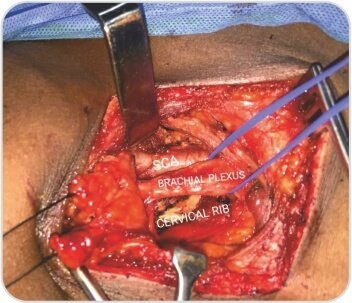

মূল্যায়নে তার ডান সম্পূর্ণ সার্ভিকাল রিব সহ ধমনী থোরাসিক আউটলেট সিন্ড্রোম পাওয়া গেছে। তাকে প্রাথমিকভাবে অ্যান্টিকোঅ্যাগুলেশন দিয়ে পরিচালিত করা হয়েছিল এবং পরে থোরাসিক আউটলেট ডিকম্প্রেশনের জন্য নেওয়া হয়েছিল। ইন্ট্রাঅপারেটিভভাবে রোগীর স্কেলিন পেশী হাইপারট্রফি এবং একটি সম্পূর্ণ জরায়ুর পাঁজর একটি বিস্তৃত প্রথম পাঁজরের সাথে মিশে গেছে যা সাবক্ল্যাভিয়ান ধমনী সংকোচন ঘটায়। ডিকম্প্রেশন পদ্ধতি অনুসরণ করে রোগীর একটি সফল ফলাফল ছিল।

জরায়ুর মুখ এবং প্রথম পাঁজর কাটা